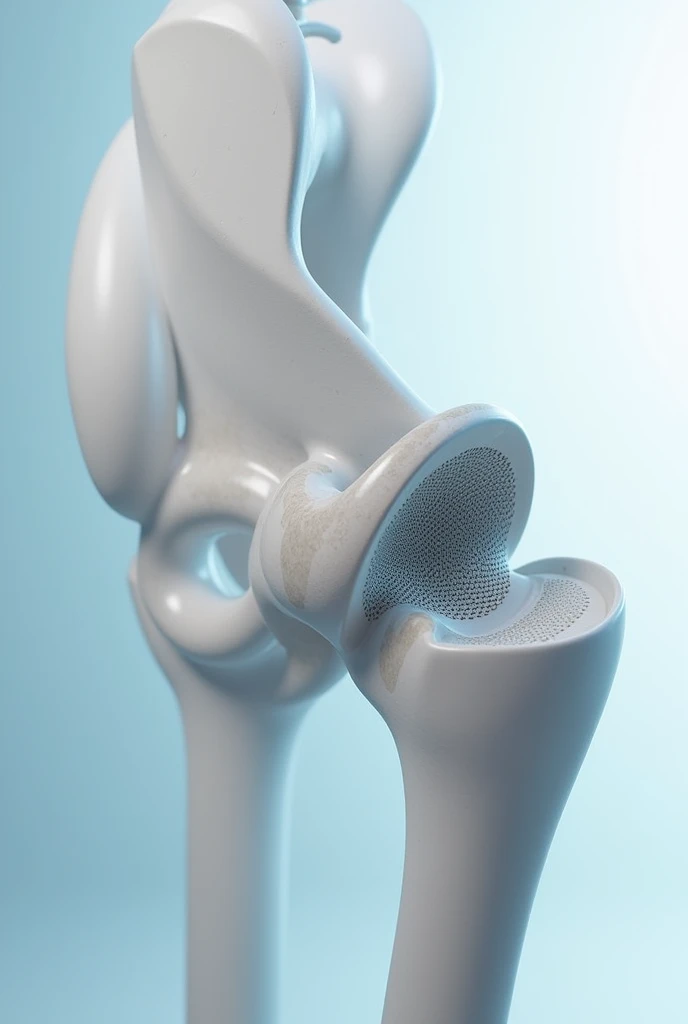

A close up of a white object with a human leg

Close-up of human knee,There is a bone in the middle, knee, Knees, surreal bone structure, Protruding bones, Realphotos, orthographic view, Look across the shoulder, medical depiction, Osteoarticular joints, computer generated, hyper realisitc, sharp bone structure, joint, digital painted